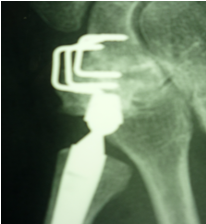

The final option is CMC joint arthrodesis. Most articles about this procedure date from the seventies and eighties, and it has now largely been replaced by arthroplasty. However, the technique should not be abanded, because it may be a viable alternative for young patients whose job involves heavy labour. The inability to bend the thumb is largely outweighed by significant gains in strength and little or no residual pain. Patients must be informed that, sooner or later, the STT arthritis will however get worse.

Figure 12 shows a patient aged about 60 who since 2008 has done a particularly manual job (construction industry) involving heavy loads, repetitive gestures, hammering etc. His doctor suggested CMC arthrodesis due to the mechanical restrictions which meant an implant was almost certainly infeasible. This was a wise decision, because the patient was able to continue working despite having limited movement in the thumb, with no significant pain.